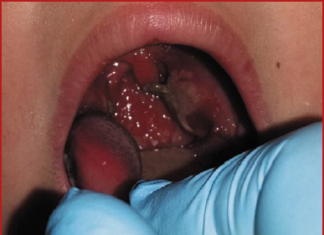

Одним из ведущих клинических проявлений ОРИ является развитие воспалительного процесса в тканях глотки и миндалин, что в медицинской литературе описывается терминами «острый фарингит» и «тонзиллит». Общность этиологии и клинических проявлений острых тонзиллита и фарингита...